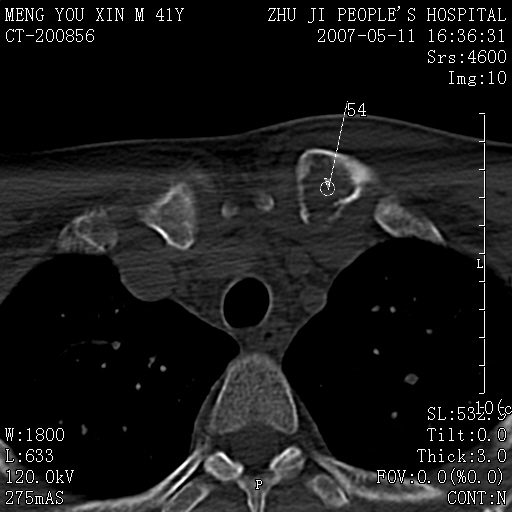

标题: CT8190:左锁骨胸骨端骨病,请会诊.

一周前左肩部酸痛,三天前颈部扭伤,后颈部摄片示颈椎病.现胸锁关节处肿痛明显.无发热.自诉三年前车祸安全气囊弹出.

左侧锁骨近端膨大,骨皮质中断,并见少许骨膜反应,内见破坏,边缘见筛孔征,无硬化.因此考虑骨巨细胞瘤可能.

1,不支持结核,此例胸壁肿胀不明显,锁骨后方是局限性肿物而非脓肿,考虑为恶性肿瘤2,左侧锁骨近端膨大,骨皮质中断,并见少许骨膜反应,内见破坏,边缘见筛孔征,无硬化.因此考虑骨巨细胞瘤可能.